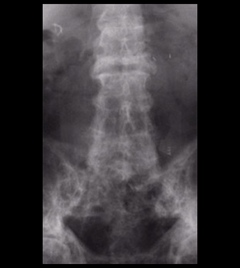

Spine

Figure 3: Paget's disease of the spine. The white, patchy appearance of the bone on this X-ray is characteristic of the dense but disordered bone in this disease.

Paget’s disease of the spine. The white, patchy appearance of the bone is characteristic of the dense but disordered bone in this disease.